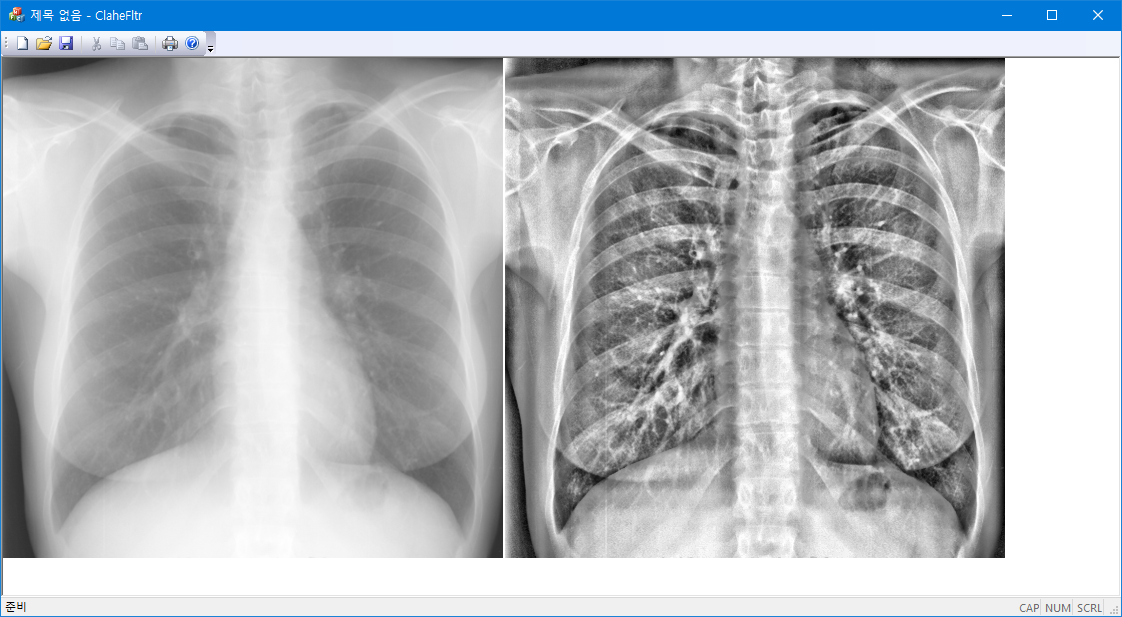

원본:

*global:

*local: wsize=51;

** CLAHE 적용: tile size = 20x 20